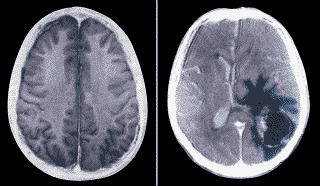

-Ensayan una vacuna celular personalizada contra los tumores cerebrales

La Clínica Universidad de Navarra ha iniciado un ensayo clínico para valorar la eficacia de un tratamiento de inmunoterapia que consiste en la aplicación de vacunas personalizadas, producidas con células sanas y tumorales del propio paciente, dirigido a tratar glioblastomas, uno de los tumores cerebrales malignos "más agresivos y frecuentes".

La nueva terapia se administra a los pacientes combinada con el tratamiento estándar para tratar esta clase de tumores que consiste en la extirpación quirúrgica del tumor seguida de la administración de radioterapia y quimioterapia con temozolomida, según explicó en rueda de prensa uno de los especialistas encargados del estudio José Javier Aristu. Este nuevo tratamiento está dirigido a pacientes recién diagnosticados de glioblastoma o con sospecha de sufrirlo.

El médico especializado en Oncología Radioterápica destacó que la Clínica Universidad de Navarra es actualmente el único centro español que realiza un estudio de estas características para el que ha recibido autorización de la Agencia del Medicamento del Ministerio de Sanidad. Según manifestó, a nivel mundial menos de 200 pacientes han sido tratados con estas vacunas, que tienen como objetivo "enseñar a los linfocitos a lucha contra los restos del tumor". El glioblastoma es el tumor